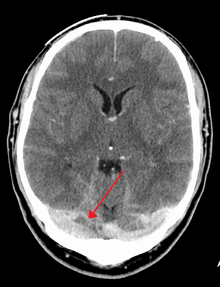

There are various neuroimaging investigations that may detect cerebral sinus thrombosis. Cerebral edema and venous infarction may be apparent on any modality, but for the detection of the thrombus itself, the most commonly used tests are computed tomography (CT) and magnetic resonance imaging (MRI), both using various types of radiocontrast to perform a venogram and visualise the veins around the brain.[1]

Computed tomography, with radiocontrast in the venous phase (CT venography or CTV), has a detection rate that in some regards exceeds that of MRI. The test involves injection into a vein (usually in the arm) of a radioopaque substance, and time is allowed for the bloodstream to carry it to the cerebral veins - at which point the scan is performed. It has a sensitivity of 75-100% (it detects 75-100% of all clots present), and a specificity of 81-100% (it would be incorrectly positive in 0-19%). In the first two weeks, the "empty delta sign" may be observed (in later stages, this sign may disappear).[5]